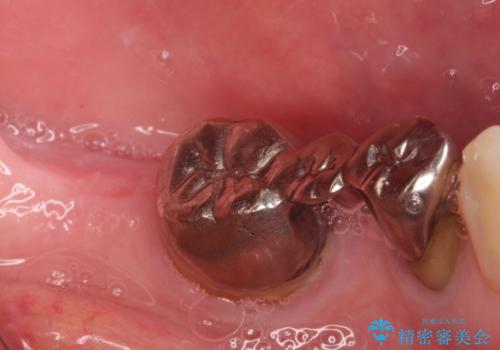

金属のかぶせ物をセラミックへ 根管治療からの再治療

左側の上下の奥歯に適合が悪く、レントゲン上でも根の治療が必要なところがありました。

再治療を行いました。